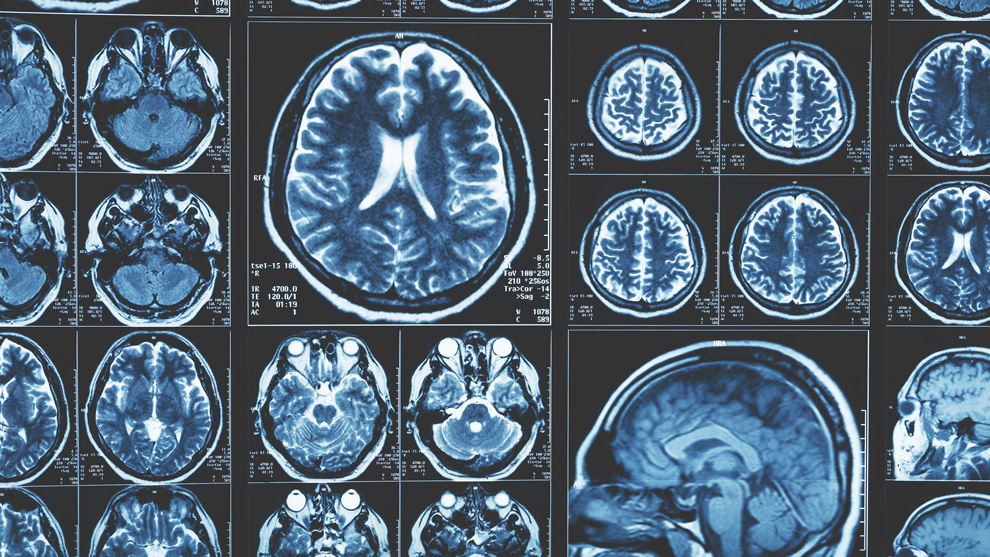

The new approach requires just one of these – a magnetic resonance imaging (MRI) brain scan taken on a standard 1.5 Tesla machine, which is commonly found in most hospitals.

The researchers adapted an algorithm developed for use in classifying cancer tumours, and applied it to the brain. They divided the brain into 115 regions and allocated 660 different features, such as size, shape and texture, to assess each region. They then trained the algorithm to identify where changes to these features could accurately predict the existence of Alzheimer’s disease.

Using data from the Alzheimer’s Disease Neuroimaging Initiative, the team tested their approach on brain scans from over 400 patients with early and later stage Alzheimer’s, healthy controls and patients with other neurological conditions, including frontotemporal dementia and Parkinson’s disease. They also tested it with data from over 80 patients undergoing diagnostic tests for Alzheimer’s at Imperial College Healthcare NHS Trust.

They found that in 98 per cent of cases, the MRI-based machine learning system alone could accurately predict whether the patient had Alzheimer’s disease or not. It was also able to distinguish between early and late-stage Alzheimer’s with fairly high accuracy, in 79 per cent of patients.